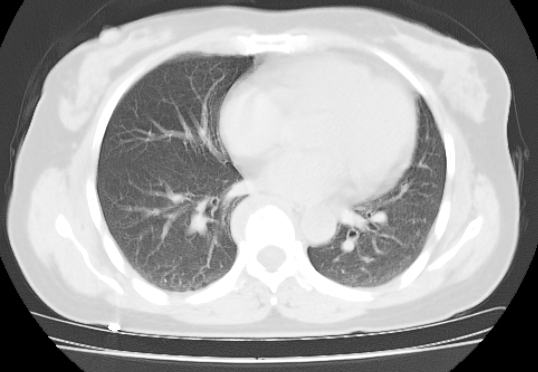

标题: CT25227:背部疼痛伴双侧胸壁痛2月,食欲差。 [打印本页]

标题: CT25227:背部疼痛伴双侧胸壁痛2月,食欲差。

肺结核并胸椎结核?请各位高手指教。

用椎体的条件来扫胸椎呀!考虑1左侧胸膜小结节形成2椎体结核并冷脓肿形成

左肺结核灶,胸椎结核并冷脓肿。

支持!不排除骨原发淋巴瘤肺内转移。

食道癌并胸椎及肺内转移